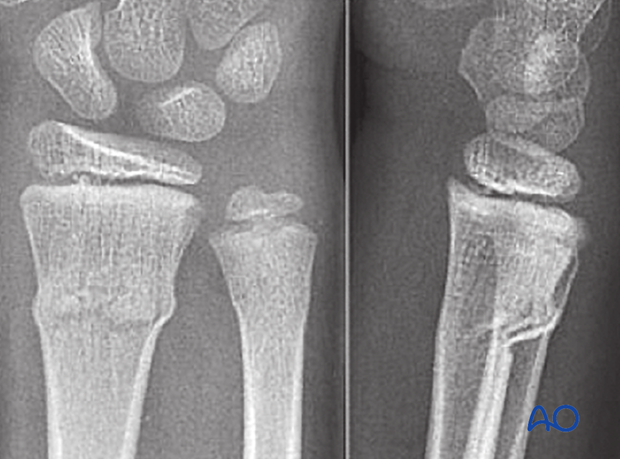

What type of fracture is this? What patient group is often seen in? What type of force causes it?

Torus fracture, also known as buckle fracture → incomplete fracture of shaft of a long bone that is characterised by bulging of cortex. They result from trabecular compression due to an axial loading force along the long axis of bone

children